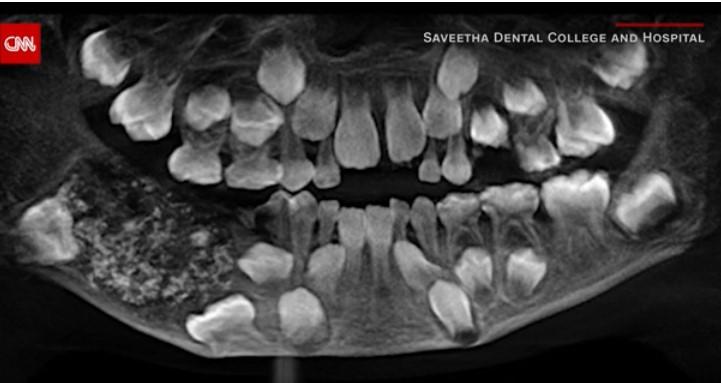

Când i-au făcut radiografie, doctorii au constatat că acesta avea „un sac” în maxilar plin cu „dinți anormali”. După o operație de aproape 5 ore, medicii au anunțat că au identificat nu mai puțin de 526 de dinți.

„În total au fost 526 de dinți având dimensiuni de la 0,1 milimetri la 15 milimetri. Chiar și cea mai mică bucată avea o coroană, rădăcină și un strat de smalț, indicând astfel că este un dinte”, a declarat unul dintre medici, potrivit CNN.